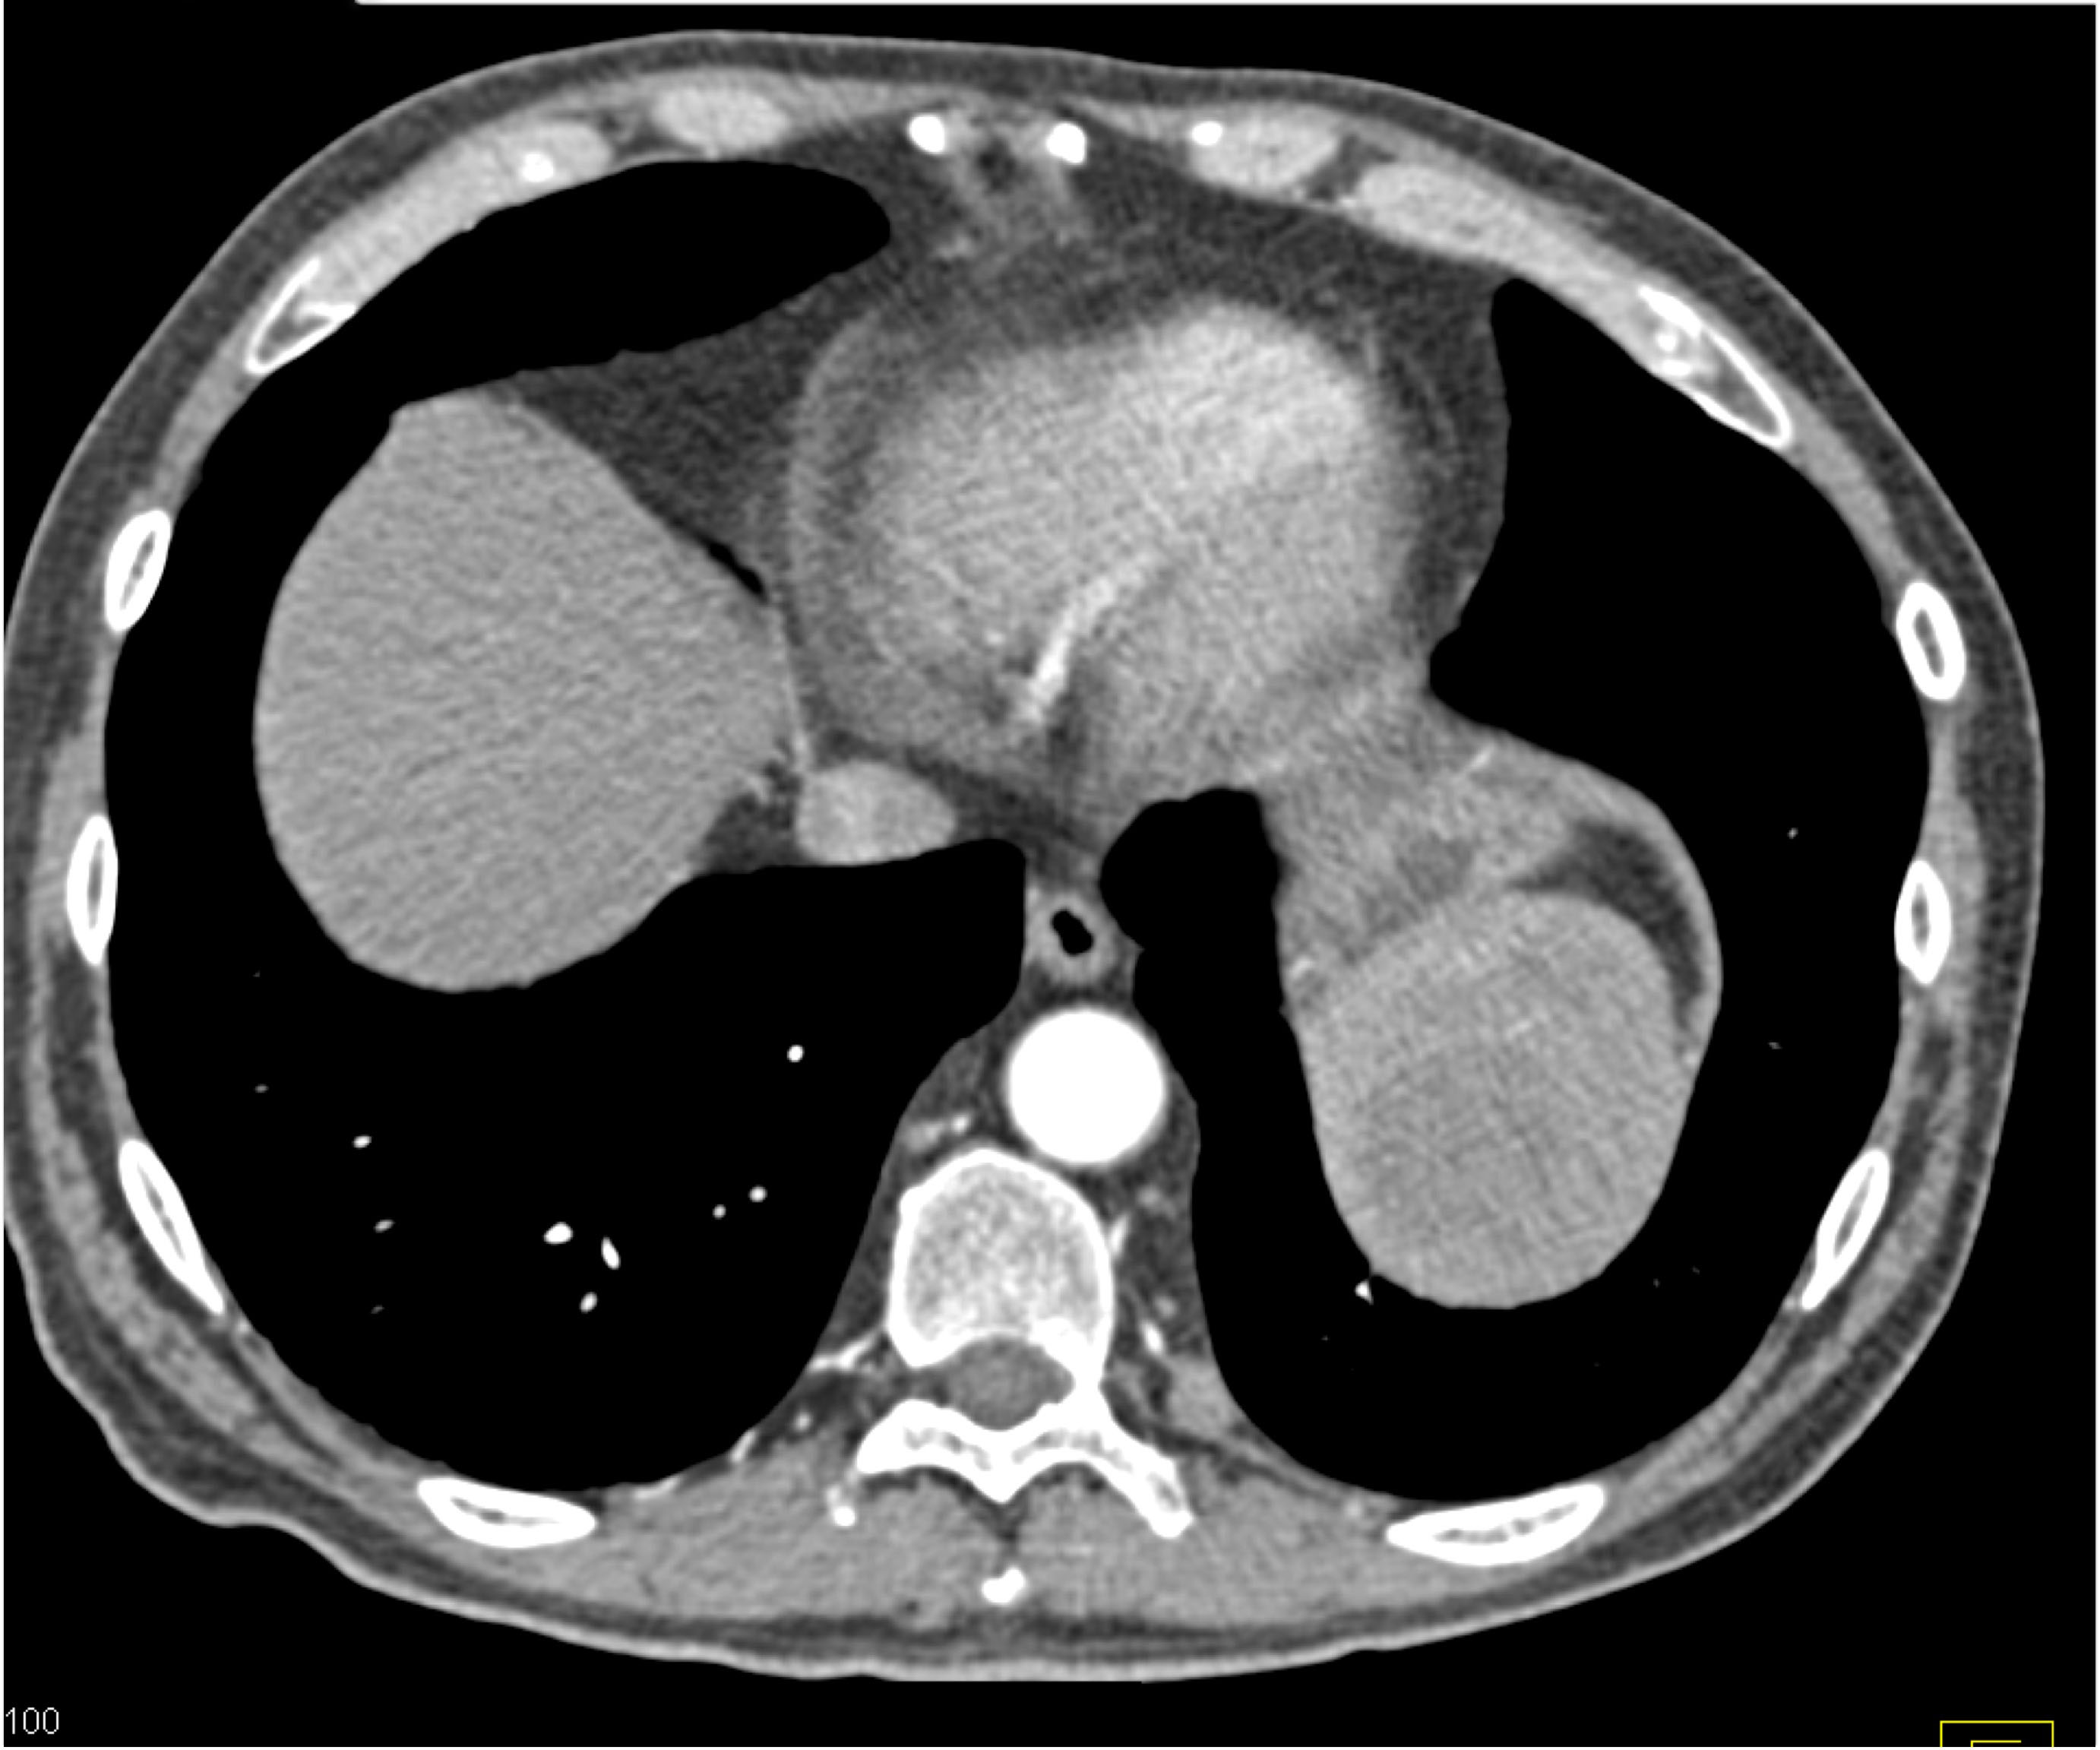

- Evaluate the CT images of each question carefully.

- Click on thumbnail images to view a larger version of the images.

- Take time to make the call on the diagnosis for each individual question.